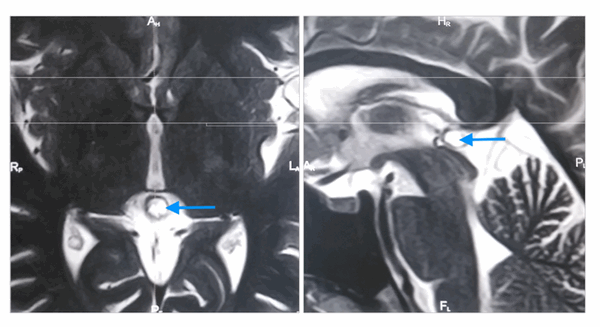

Киста шишковидной железы с типичным гиперинтенсивным сигналом на МРТ (Т2 ВИ) (отмечена синей стрелкой). Слева: аксиальная томограмма, справа - сагиттальная

На МРТ наблюдаются следующие признаки:

- Типичный изо- или гипоинтенсивный сигнал по сравнению с паренхимой головного мозга

- В 55-60% случаев гиперинтенсивный сигнал по сравнению с ликвором

- Сигнал обычно однородный

- Сигнал высокой интенсивности

- Обычно слегка менее интенсивный по сравнению с ликвором

- Сигнал высокой интенсивности, который часто не подавляется полностью

- Рестрикция диффузии отсутствует

- Примерно 60% кист накапливают контраст

- Накопление контраста в большинстве случаев происходит в виде тонкого (меньше 2 мм) и ровного «ободка» (полного или неполного)

- Возможно диффузное контрастное усиление жидкостного содержимого кисты препаратами на основе гадолиния в отсроченной фазе (60-90 минут), вследствие чего киста становится похожей на солидное объемное образование

- Редко может обнаруживаться нетипичное узловое контрастное усиление, также могут определяться признаки кровоизлияния в кисту